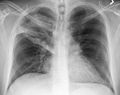

A Xray showing a white wedge in the right lung field of a chest X-ray.

A chest X-ray showing a very prominent wedge shaped pneumonia in the right lung.